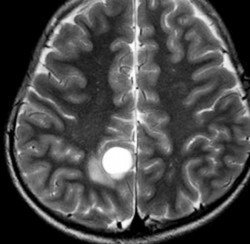

小脳毛様細胞性星細胞腫のFLAIR画像所見

壁在結節を伴うのう胞性小脳毛様細胞性星細胞腫は,結節を手術摘出すれば治癒するものです。しかし,あたかも腫瘍が残っているようなMRI画像所見が残ることがあります。

この例は,10歳の子どもに無症状で偶然発見された大きなのう胞性小脳毛様細胞性星細胞腫です。開頭手術で腫瘍結節は全摘出して腫瘍のう胞は縮小したままです。(画像はクリックすると拡大して見えます)

開頭手術で白く増強される結節部分だけを摘出しました。MIB-1はやや高値で3%と報告されました。病理組織診断は,WHO grade 1 毛様細胞性星細胞腫です。

6年後のMRI FLAIR画像です。摘出腔周囲の高信号域が残存しています。ここまで残ると腫瘍周辺浮腫ではありませんし,腫瘍細胞が左小脳半球に広範囲に浸潤して残存しているものだと判断されます。しかし,6年間で病変の増大傾向がありませんでした。この残存腫瘍(らしい所見)に対して放射線治療や化学療法を行うべきかどうか,結論は出ていません。しかし,経過観察を続けても増大して来ない例があることは確かです。一方で,この高信号領域が拡大したり,ガドリニウム増強される病変が再出現して治療がまた必用となることもあります。